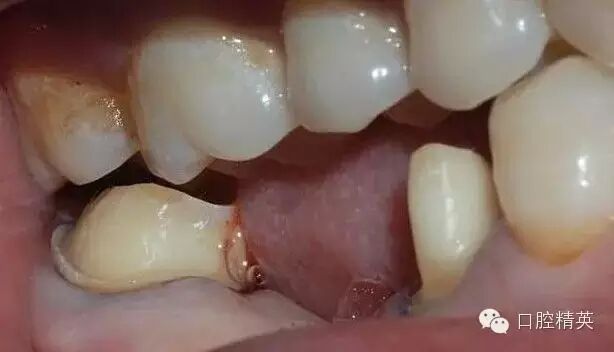

46缺失,不考慮種植牙,45、47做基牙,固定烤瓷橋修復;這是口內的情況

咬合時的情況